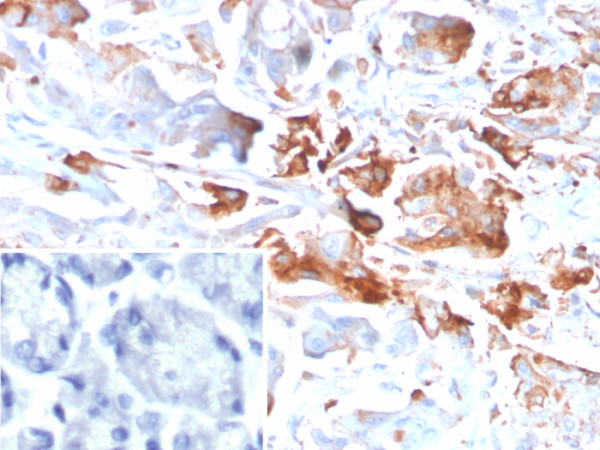

Product information "Anti-CEACAM1 (CEA Cell Adhesion Molecule 1), clone CEACAM1/4840"

Formulation: Purified Ab with BSA and Azide at 200ug/ml. Cellular Localization: Secreted. Cell membrane. Localizes to sites of cell-cell contact. Positive Control: endometrium, Human: colon, liver or hepatic carcinoma tissues. Chromosome Location: 19q13.2. Protein Function: Cell adhesion protein that mediates homophilic cell adhesion in a calcium-independent manner (By similarity). Plays a role as coinhibitory receptor in immune response, insulin action and also functions as an activator during angiogenesis (PubMed:18424730, PubMed:23696226, PubMed:25363763). Its coinhibitory receptor function is phosphorylation- and PTPN6 -dependent, which in turn, suppress signal transduction of associated receptors by dephosphorylation of their downstream effectors. Plays a role in immune response, of T cells, natural killer (NK) and neutrophils (PubMed:18424730, PubMed:23696226). Upon TCR/CD3 complex stimulation, inhibits TCR-mediated cytotoxicity by blocking granule exocytosis by mediating homophilic binding to adjacent cells, allowing interaction with and phosphorylation by LCK and interaction with the TCR/CD3 complex which recruits PTPN6 resulting in dephosphorylation of CD247 and ZAP70 (PubMed:18424730). Also inhibits T cell proliferation and cytokine production through inhibition of JNK cascade and plays a crucial role in regulating autoimmunity and anti-tumor immunity by inhibiting T cell through its interaction with HAVCR2 (PubMed:25363763). Upon natural killer (NK) cells activation, inhibit KLRK1-mediated cytolysis of CEACAM1-bearing tumor cells by trans-homophilic interactions with CEACAM1 on the target cell and lead to cis-interaction between CEACAM1 and KLRK1, allowing PTPN6 recruitment and then VAV1 dephosphorylation (PubMed:23696226). Upon neutrophils activation negatively regulates IL1B production by recruiting PTPN6 to a SYK-TLR4-CEACAM1 complex, that dephosphorylates SYK, reducing the production of reactive oxygen species (ROS) and lysosome disruption, which in turn, reduces the activity of the inflammasome. Down-regulates neutrophil production by acting as a coinhibitory receptor for CSF3R by down-regulating the CSF3R-STAT3 pathway through recruitment of PTPN6 that dephosphorylates CSF3R (By similarity). Also regulates insulin action by promoting INS clearance and regulating lipogenesis in liver through regulating insulin signaling (By similarity). Upon INS stimulation, undergoes phosphorylation by INSR leading to INS clearance by increasing receptor-mediated insulin endocytosis. This inernalization promotes interaction with FASN leading to receptor-mediated insulin degradation and to reduction of FASN activity leading to negative regulation of fatty acid synthesis. INSR-mediated phosphorylation also provokes a down-regulation of cell proliferation through SHC1 interaction resulting in decrease coupling of SHC1 to the MAPK3/ERK1-MAPK1/ERK2 and phosphatidylinositol 3-kinase pathways (By similarity). Functions as activator in angiogenesis by promoting blood vessel remodeling through endothelial cell differentiation and migration and in arteriogenesis by increasing the number of collateral arteries and collateral vessel calibers after ischemia. Also regulates vascular permeability through the VEGFR2 signaling pathway resulting in control of nitric oxide production (By similarity). Down-regulates cell growth in response to EGF through its interaction with SHC1 that mediates interaction with EGFR resulting in decrease coupling of SHC1 to the MAPK3/ERK1-MAPK1/ERK2 pathway (By similarity). Negatively regulates platelet aggregation by decreasing platelet adhesion on type I collagen through the GPVI-FcRgamma complex (By similarity). Inhibits cell migration and cell scattering through interaction with FLNA. interferes with the interaction of FLNA with RALA (PubMed:16291724). Mediates bile acid transport activity in a phosphorylation dependent manner (By similarity). Negatively regulates osteoclastogenesis (By similarity) , Cell adhesion protein that mediates homophilic cell adhesion in a calcium-independent manner (By similarity). Promotes populations of T cells regulating IgA production and secretion associated with control of the commensal microbiota and resistance to enteropathogens (By similarity) [The Uniprot Consortium]

| Application: | IHC |